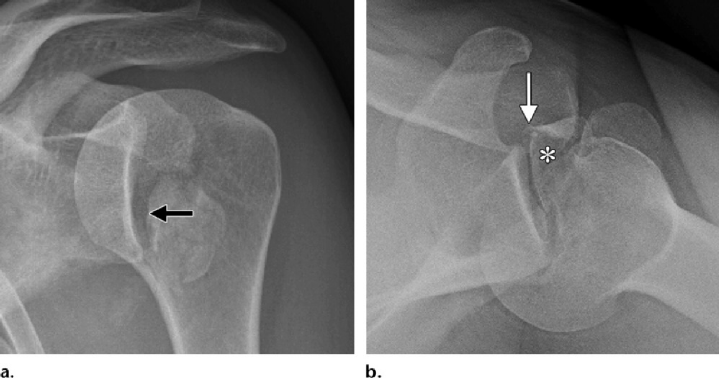

It is standard procedure to take simple anteroposterior radiographs both before and after a dislocation. Anteroposterior radiographs are the only imaging tests often performed during an emergency. Doctor usually perform axillary and/or transcapular projection if they suspect a posterior dislocation, even they don’t know which way the force is coming from. There is a 50% chance that anteroposterior radiography will overlook posterior dislocations. In the absence of other perspectives, a multitude of frontal indicators may be used to identify posterior dislocation. At the location of the impact fracture on the anterior humeral head, a sclerotic line may be seen in the axillary view. Reason being, a 6 mm or greater rise in the articular distance indicates either the trough indication or the rim sign.14

When the direction of the force cannot be determined, CT imaging is the suggested method. Dislocation in conjunction with a bony-Bankart lesion and a larger tuberosity fracture are also covered in depth. CT scans, using the best-fit circle method in the sagittal plane, provide the most precise evaluation of glenoid injury. It is crucial to diagnose glenoid bone loss because instability is likely to occur when a defect affects more than 20% of the entire glenoid surface or more than 7 mm in width.15

Because the current idea is that the rotator cuff muscles displace independent pieces, the simplest tests are used to image proximal humerus fractures. It has been demonstrated that the axillary view in conjunction with the anteroposterior view improves classification accuracy. Both the intraobserver and interobserver reliability of current categories, including the AO/Orthopedic Trauma Association and Neer, are low, regardless of the imaging modalities utilized. In addition, surgeons often use 3D CT to evaluate complicated fracture patterns, even though some authors claim that these studies show higher intraobserver and interobserver agreement. Because of this, not even shoulder experts can determine the best imaging approach to accurately detect fractures by balancing categorization. In addition, the Neer classification of the four segments is not based on radiographic data. The pathoanatomical categorization that is attained by exact x-ray studies, film interpretation, and sometimes intraoperative results forms its basis.16

Other, more important criteria that are best evaluated with CT scans include articular surface separation, humeral head impaction, and segment rotation. With the identification of valgus rotation of the humeral head among isolated segments of the tuberosities, a new form of valgus-impacted four-part fracture was introduced to the Neer classification in 2002. In these cases, the glenohumeral articular surface is maintained, instead of the usual four-part proximal humerus fracture. The nutritive arteries penetrate the bone and deliver perfusion to the arcuate vessels via an unbroken medial calcar, reducing the risk of post-traumatic avascular necrosis. Surgery is not always necessary to treat this issue.17